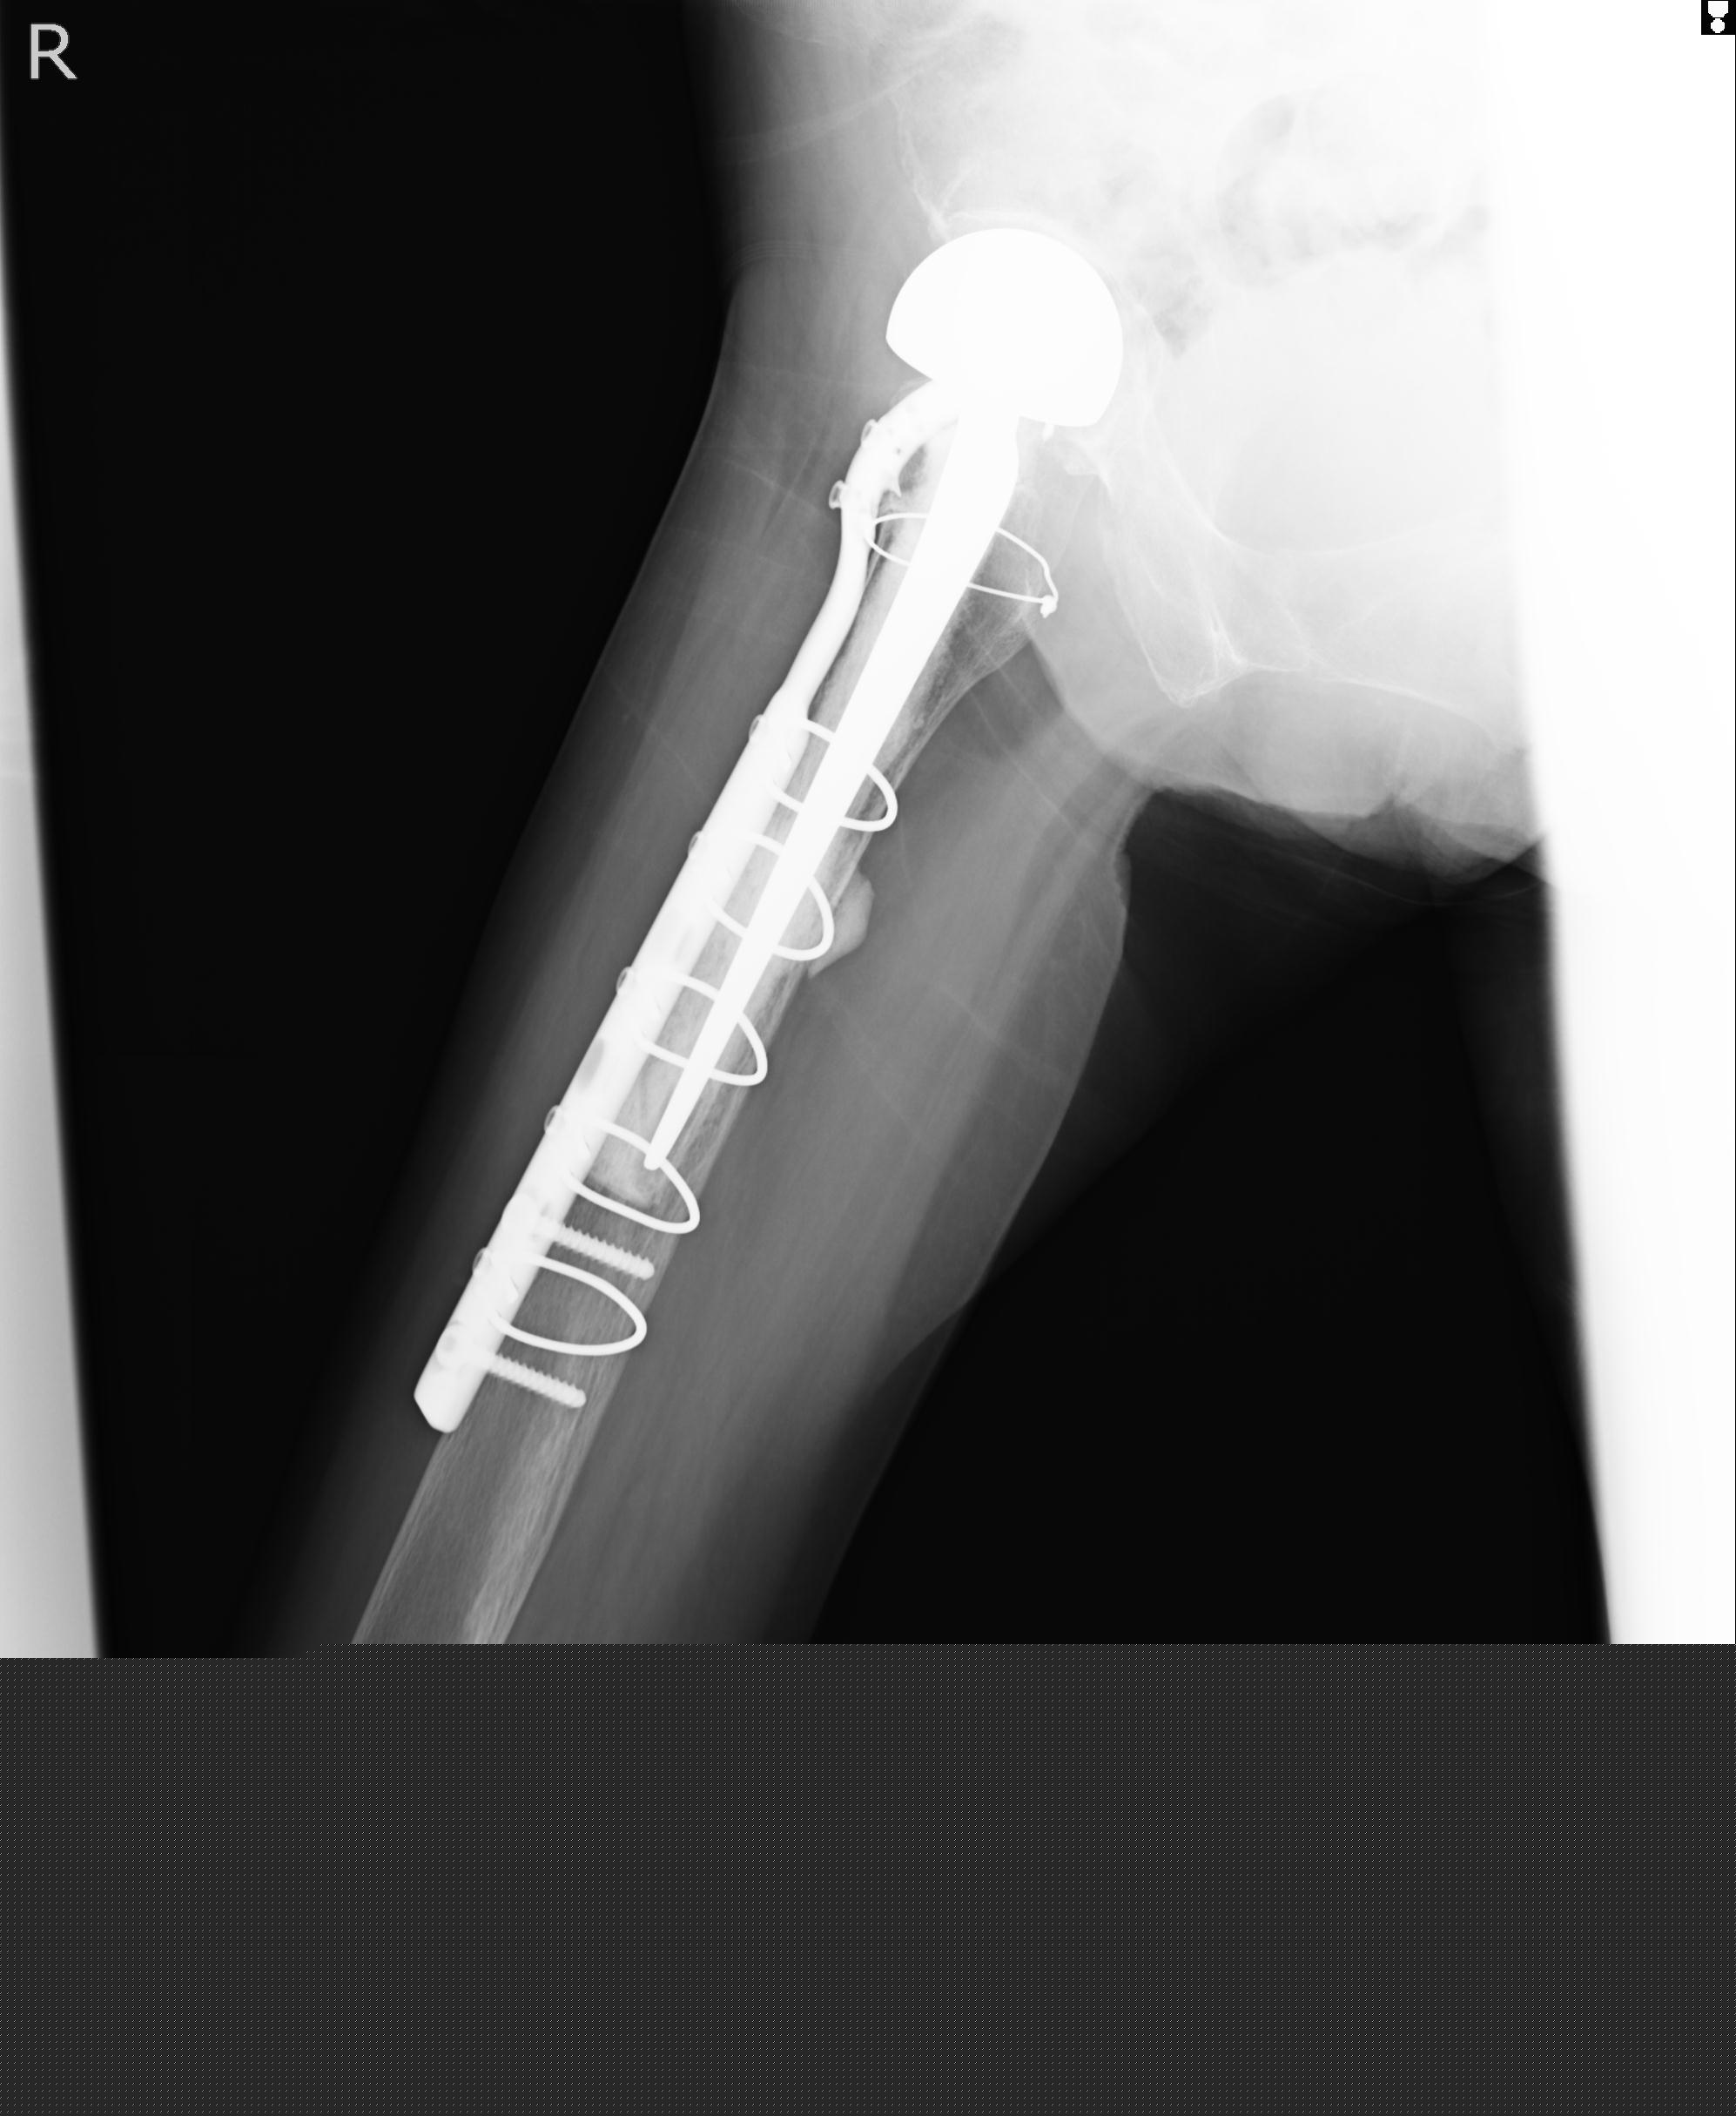

110286 2/17 股関節 2R 74歳女性 右人工骨頭